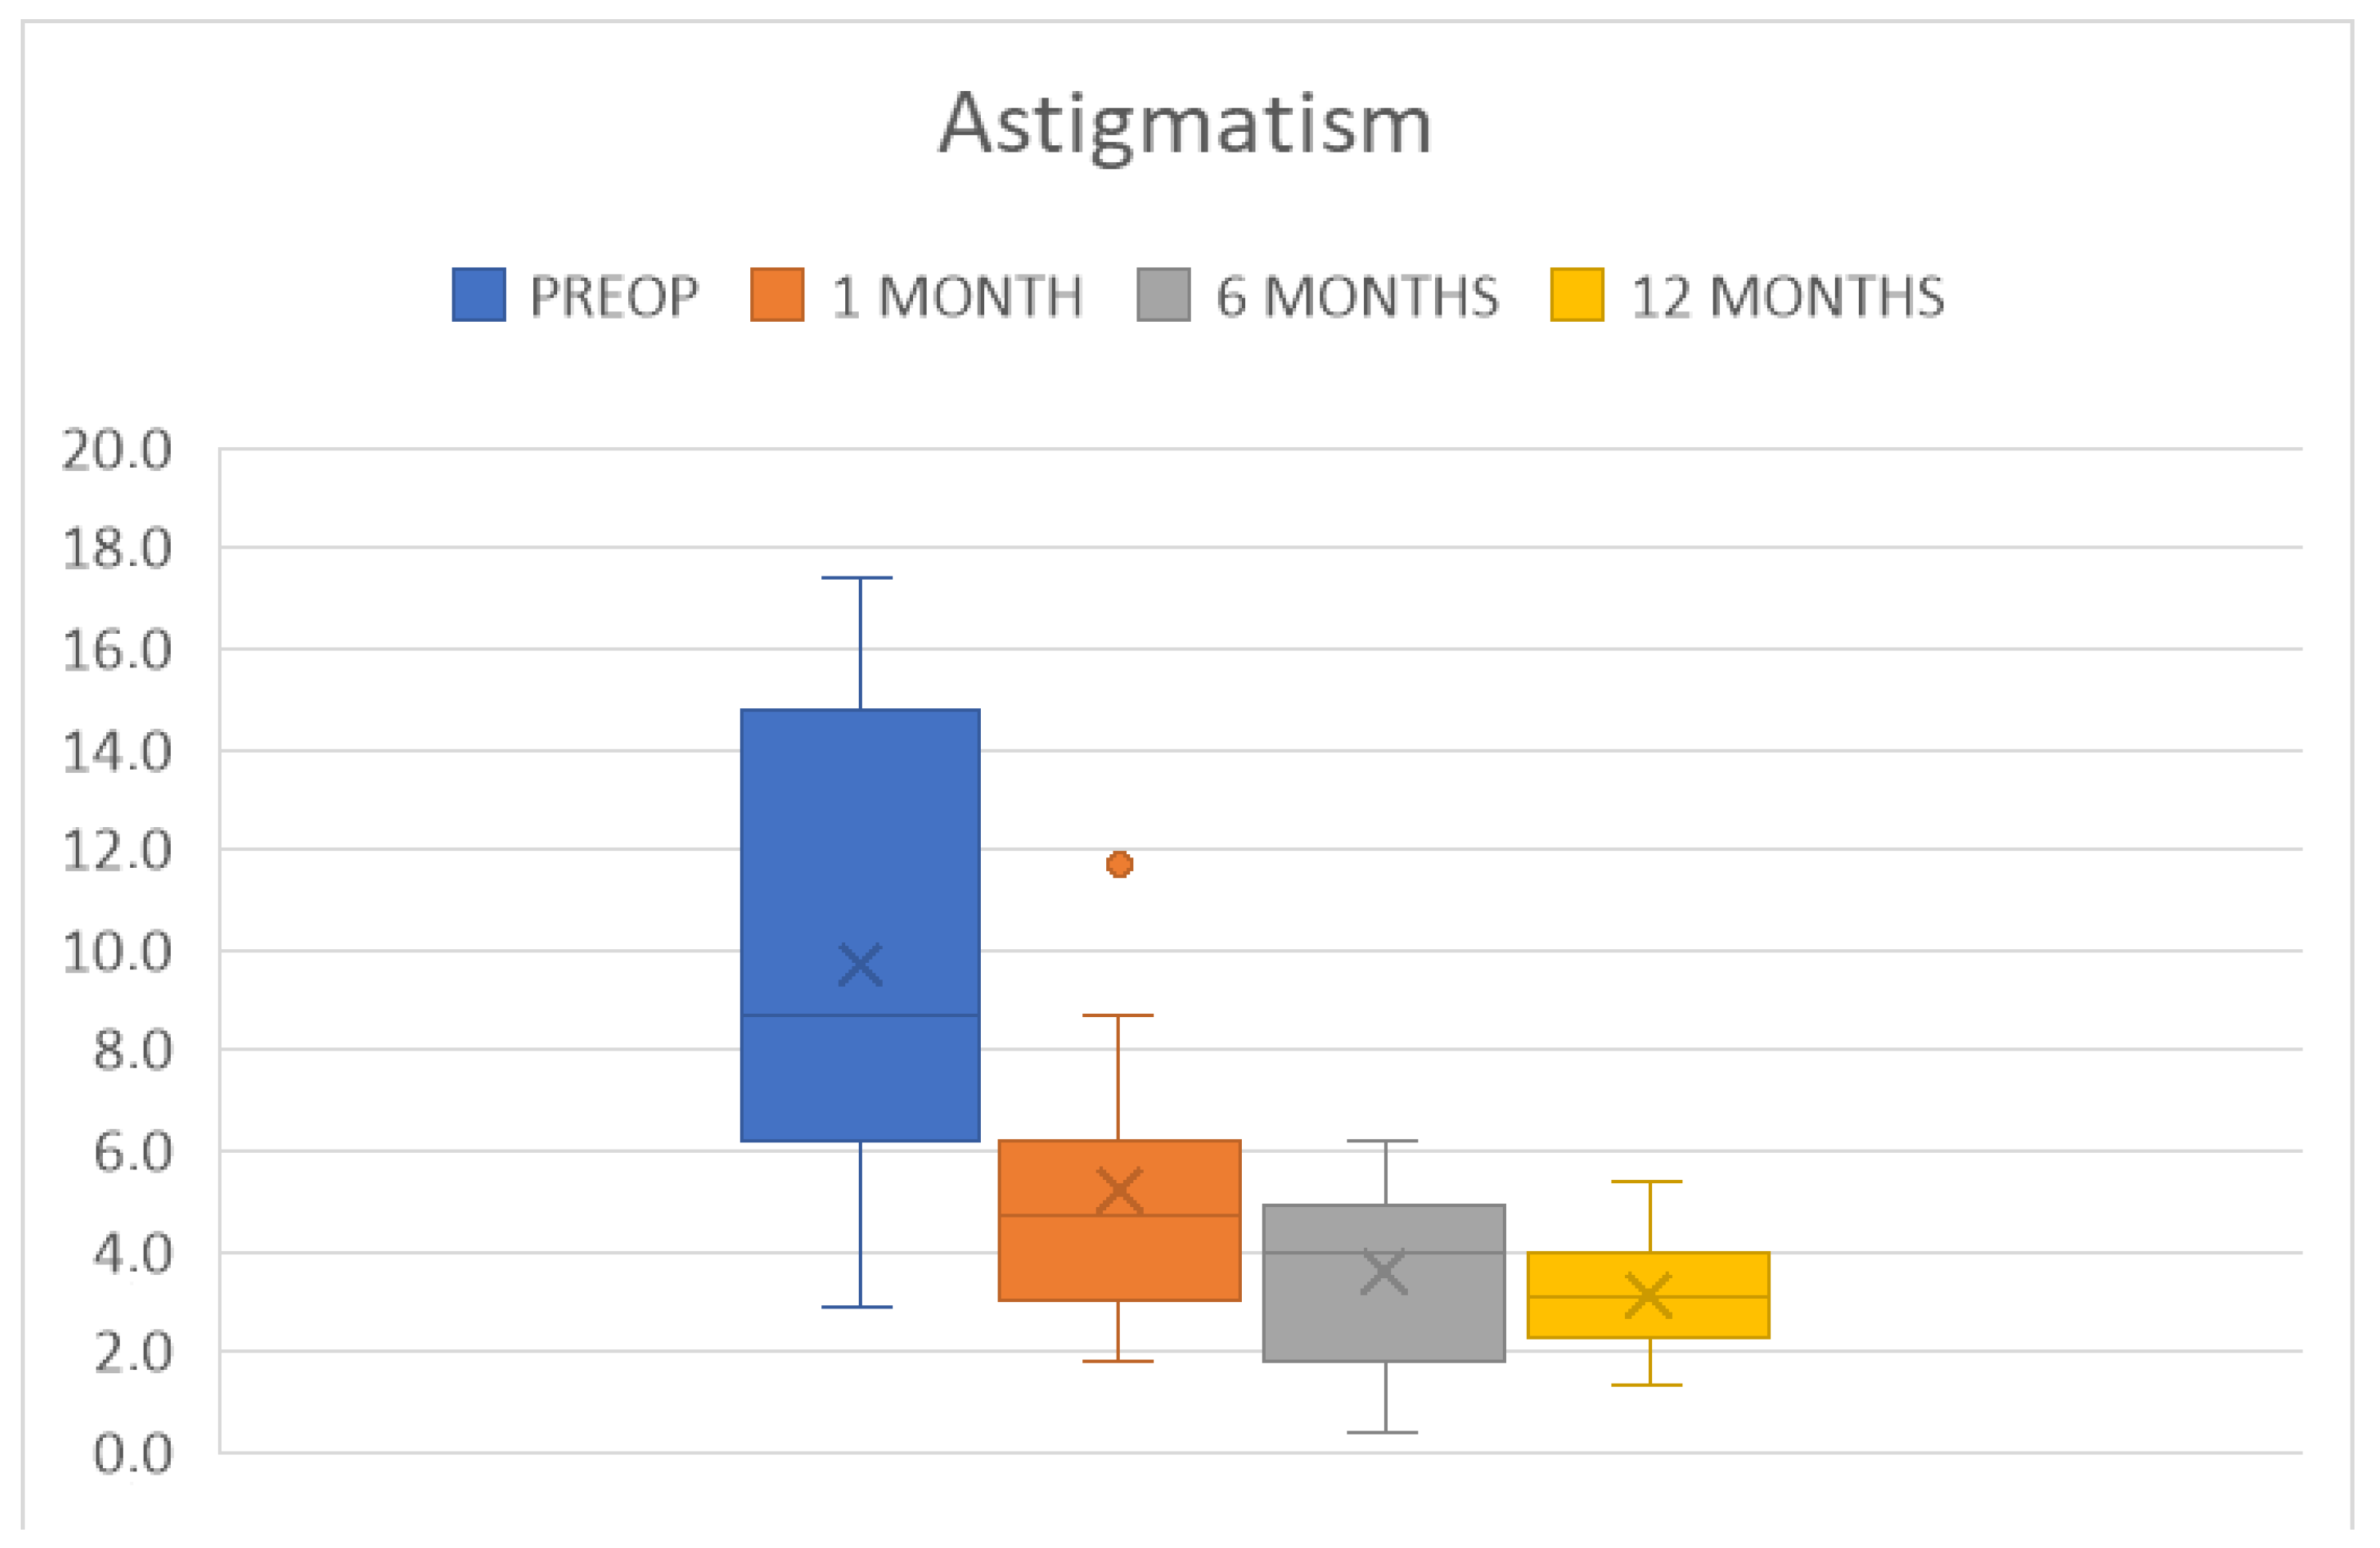

4. Results

| Parameter Measured | 6 Months | 12 Months | ||

|---|---|---|---|---|

| BCVA (LogMAR) | 0.5 ± 0.3 | p < 0.0001 | 0.3 ± 0.2 | p < 0.0001 |

| CCT (µm) | 528 ± 46 | p < 0.0001 | 532 ± 45 | p = 0.0001 |

| ECD (cells/mm2) | 2181 ± 190 | 1926 ± 199 | ||

| KMIN (D) | 41.7 ± 1.8 | p < 0.001 | 42.0 ± 1.2 | p = 0.001 |

| KMAX (D) | 45.3 ± 1.5 | p < 0.0001 | 45.1 ± 1.2 | p < 0.0001 |

| AVK (D) | 43.5 ± 1.4 | p < 0.0001 | 43.5 ± 1.1 | p < 0.0001 |